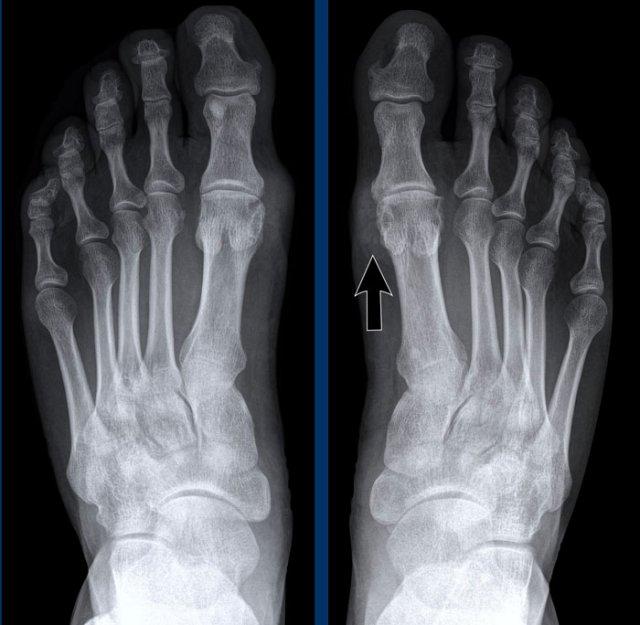

Tỷ trọng mô mềm

Sưng mô mềm tăng tỷ trọng điển hình bao quanh khớp MTP1 hai bên.

Bào mòn cạnh khớp ở mặt trong của đầu xương bàn chân (MT) phía xa, có viền xơ cứng.

Tổn thương rõ nhất ở bên phải (mũi tên).

Tiếp tục với hình ảnh CT Năng lượng kép (Dual Energy CT)…

CT Năng lượng kép (Dual Energy CT) của cùng bệnh nhân gout cho thấy các vùng lắng đọng tinh thể urat.

Trong hình tái dựng 3D này, các vùng lắng đọng tinh thể được mã hóa màu xanh lá và có thể thấy bao quanh các khớp MTP và tại điểm bám của gân Achilles bên phải (mũi tên).

Các điểm ảnh màu xanh ở giường móng của ngón 1 và ngón 5 bên trái là xảo ảnh do keratin trong móng dày.

CT Năng lượng kép là phương pháp không xâm lấn để phát hiện tinh thể urat, có thể thay thế chọc hút dịch khớp.

Một trường hợp khác với hạt tophi điển hình và bào mòn cạnh khớp trên phim X-quang thường.

CT Năng lượng kép cho thấy tín hiệu gout tại khớp MTP1, MTP2 và các khớp liên đốt ngón của ngón 3.

DECT hữu ích cho chẩn đoán khi các dấu hiệu không điển hình.

Phương pháp này cũng rất hữu ích để đánh giá mức độ lan rộng của bệnh.